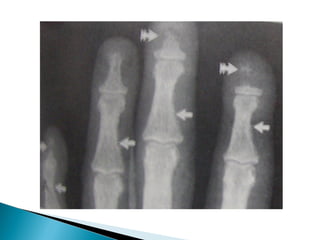

•   Subperiosteal cortical resorption of middle phalanges

Osteoporosis • Subperiosteal cortical resorption of middle phalanges • Vertebral collapse • Brown tumors • Renal calculi,Nephrocalcinosis • Chondrocalcinosis